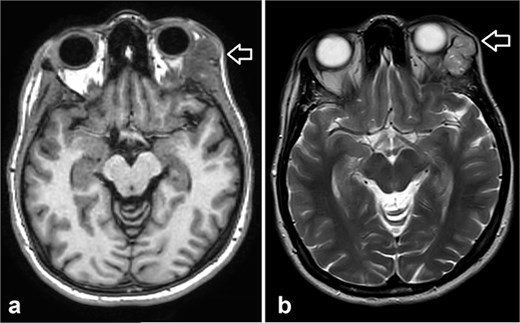

Orbit MRI showed lobulated well-defined lesion, hyperintense to intermediate on T2W (a), hypointense on T1W (b) structures with cystic changes measuring 2 × 1.5 cm and 2 × 1.2 cm. After IV contrast administration they showed heterogeneous moderate enhancement.

MRI is the preferred modality to detect bony invasion and perineural spread. ACC usually appears as T1 isointense and T2 hyperintense with enhancement . Our patient's orbit MRI showed a lobulated, well-defined lesion, hyperintense to intermediate on T2W and hypointense on T1W structures with cystic changes.